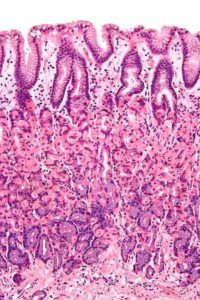

- Histología. El recto es la porción del tubo digestivo que continúa al colon. Su conformación celular es casi idéntica a este. En su estudio macroscópico se observan cuatro estratos o capas, que son: mucosa, sub-mucosa, muscular y serosa. La capa mucosa tiene células de tipo cilíndrico simple. Esto quiere decir que posee una sola capa de células altas y redondas. Las válvulas de Houston son repliegues mucosos, por lo tanto, sus células son también cilíndricas simples. A pesar de que las válvulas de Houston son pliegues formados por mucosa, en estudios microscópicos especializados se ha encontrado que contienen fibras musculares lisas. Raramente, están compuestas de epitelio mucoso y sub-mucoso únicamente. La capa sub-mucosa es donde se encuentran los vasos sanguíneos y nervios, o paquete vásculo-nervioso. El estrato sub-mucoso también forma parte de la estructura de las válvulas de Houston. La capa serosa es un revestimiento de peritoneo laxo que cubre los órganos intra-abdominales. Los dos tercios proximales del recto se encuentran cubiertos con serosa, mientras el tercio distal, el más cercano al canal anal, no. La tercera válvula de Houston es la estructura anatómica que marca la división entre los dos tercios superiores y el tercio inferior del recto, es decir, que al nivel de esta válvula el recto se divide en una porción cubierta con serosa y una porción descubierta.